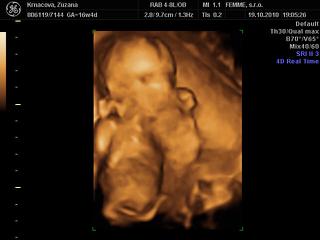

@petasllov no nas doktor nam vypocil termin na 2. april, ale po 3D a morfologii stale ultrazvuk vyhodil 1.4, ale nevadi ak to bude aj na den blaznov, hlavne nech je zdravi ved vynimka potvrdzuje pravidlo 😀 , aspon nikto nezabudne na jeho narodeniny 😵 a rodinu sme dopredu varovali, ze ak si malinky vyberie 1.4 termin a budeme im volat nech to neberu ako 1. aprilovy zart 😝